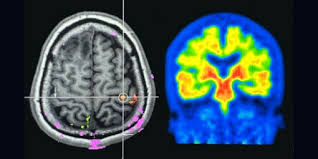

- 알츠하이머는 아밀로이드 베타 단백질과 타우 단백질의 이상 축적이 주요 원인입니다.

② 새로운 약물

- 최근 미국에서는 베타 아밀로이드 단백질을 제거하는 항체 치료제(예: 아두카누맙, 레카네맙)가 조건부 승인되어 사용되고 있습니다.